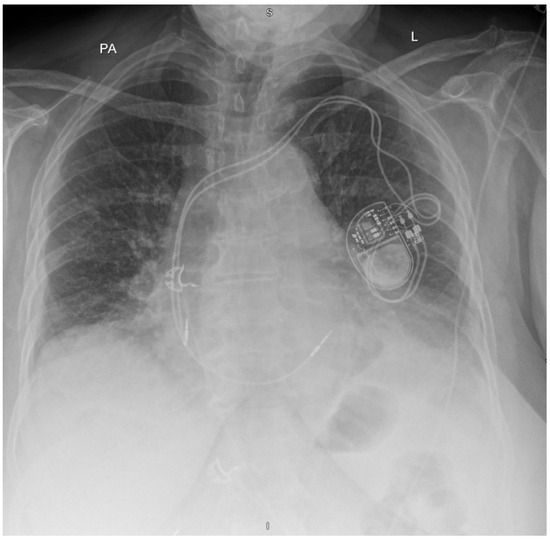

Twiddler’s Syndrome: Predictors, Prevention, and Outcomes in a Case Series

Background/Objectives: Twiddler’s syndrome is an uncommon but clinically important complication of implantable cardiac devices, in which generator rotation within the pocket results in lead torsion, lead retraction, and device malfunction. Recurrence can necessitate repeated surgical intervention and may be preventable through early risk identification and procedural strategies. Methods: We describe a single-centre case series of three female patients with pacemaker-associated Twiddler’s syndrome. Clinical presentation, timing of lead retraction, management strategies (including pocket location and fixation approach), recurrence, and follow-up outcomes were reviewed. Results: All patients were older women and developed symptomatic device failure early after implantation, with radiographic confirmation of lead retraction and coiling occurring within three weeks in all cases. Recurrence was observed when enhanced preventive measures were not employed. Notably, in one patient, recurrence occurred after an initial revision in a second prepectoral pocket, prompting subsequent reimplantation in a subpectoral location with reinforced fixation and structured patient and family counselling, after which no further recurrence occurred at one year. In the remaining cases, revision with reinforced generator fixation and counselling was associated with stable lead position and satisfactory device function during follow-up. Conclusions: Twiddler’s syndrome most commonly presents in the first weeks following implantation. Proactive identification of at-risk patients and consideration of reinforced fixation and pocket strategies at the index procedure may reduce recurrence and avoid repeat interventions.

Figure 1